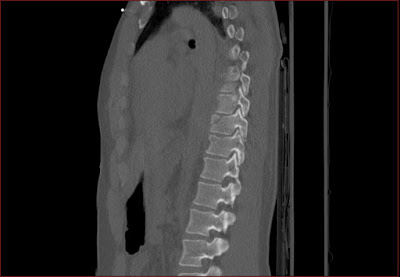

Csigolyatores a thoracalis gerincszakaszon Szerző: admin | jún 10, 2010 | Fracture, Pneumothorax, Trauma | Nincsenek hozzászólások A csigolyatest felso zarolemezt is erinto elulso torese tores a processus spinosuson